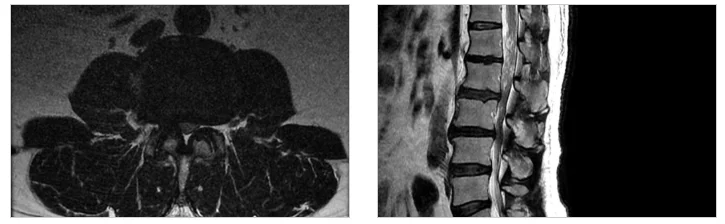

최근 허리 디스크 진단을 받고 내원하시는 분들이 늘고 있습니다. 척추내시경 수술을 고민하기 전에 가장 먼저 선행되어야 할 것은 “정말 수술이 필요한 상태인가”를 판별하는 정밀 진단입니다. 50대 남성 환자분들의 경우 퇴행성 변화와 함께 갑작스러운 외상이 겹치는 경우가 많아 MRI를 통한 정밀 분석이 필수적입니다. 저희 병원에서는 GE 3.0T MRI와 같은 고성능 장비를 활용하여 신경 압박의 정도를 0.1mm 단위까지 세밀하게 파악합니다.

척추내시경 수술로 고민하시는 분들이 가장 궁금해하시는 것은 실제 수술이 어떻게 진행되느냐 하는 점입니다. 이 수술은 고해상도 카메라가 달린 내시경을 통해 병변 부위를 10배 이상 확대하여 보면서 진행하기 때문에, 육안으로 보는 것보다 훨씬 세밀한 작업이 가능합니다. 이는 주변의 미세 혈관이나 신경 가지를 보호하는 데 매우 유리합니다.